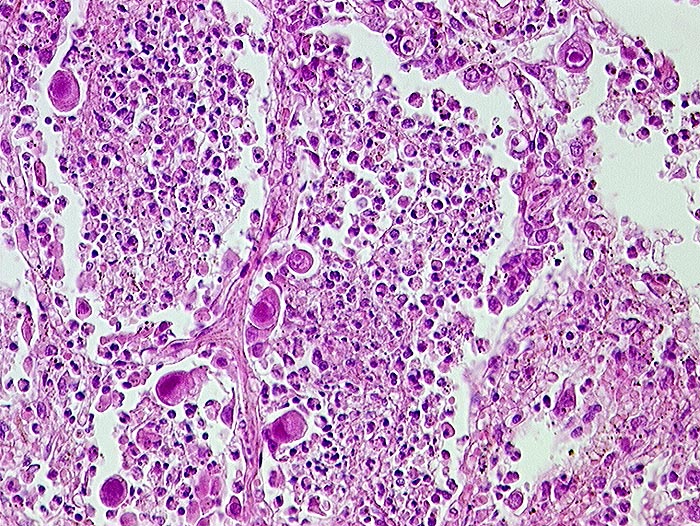

AP/ Cytomegalievirus-Infekt der Lunge

Cytomegalievirus-Infekt der Lunge

Entzündung infektiös

Lunge, Mediastinum mit Thymus

Lunge